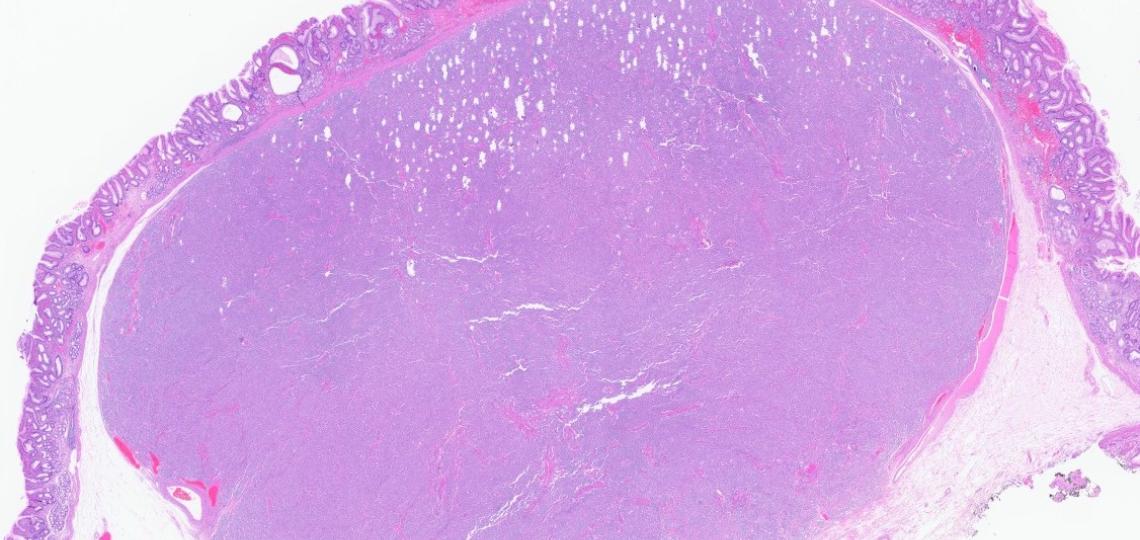

Q: An 80-year-old woman undergoes fine-needle biopsy of a pancreatic mass. Which of the following statements accurately describes SMARCA4-deficient undifferentiated pancreatic carcinoma?

Answer: E. All of the above.

Explanation:

SMARCA4-deficient undifferentiated pancreatic carcinoma (UPC) is an exceptionally rare and poorly understood subtype of pancreatic cancer, defined by loss of the SMARCA4 gene, which encodes the BRG1 protein, and characterized by highly aggressive behavior.

Please see the attached images for more context.

Undifferentiated pancreatic carcinoma (UPC) is a rare, aggressive epithelial malignancy lacking glandular differentiation or desmoplastic reaction. It frequently exhibits rhabdoid morphology.

According to the WHO classification, UPC subtypes include anaplastic, rhabdoid, sarcomatoid, and carcinosarcoma subtypes.

Unlike classic pancreatic ductal adenocarcinoma (PDAC), UPC typically demonstrates scant stroma, frequent KRAS-wild-type status, and a significantly worse prognosis.

Recent research emphasizes the role of SWI/SNF (Switch/Sucrose Non-Fermentable) chromatin remodeling complex, particularly SMARCA4 loss, in driving tumorigenesis and contributing to poor clinical outcomes.

However, SMARCA4-deficient UPC remains extremely uncommon, with limited case documentation, highlighting the need for increased recognition and development of targeted therapies.

Current management relies primarily on surgery and conventional chemotherapy, which offer limited benefits. Emerging evidence suggests potential responsiveness to immune checkpoint inhibitors in PD-L1–high tumors, especially in SWI/SNF-deficient cancers. Investigational strategies include EZH2 inhibitors and SMARCA2 degraders.

Routine immunohistochemical staining for SMARCA4, SMARCA2, and SMARCB1 is recommended in pancreatic tumors with rhabdoid morphology to identify SWI/SNF-deficient variants.